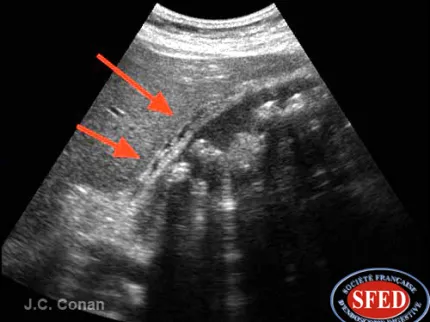

- l’échographie abdominale → foie, vésicule biliaire, voies biliaires, pancréas, reins, rate, vaisseaux, péritoine et tube digestif (examen en externe) ;